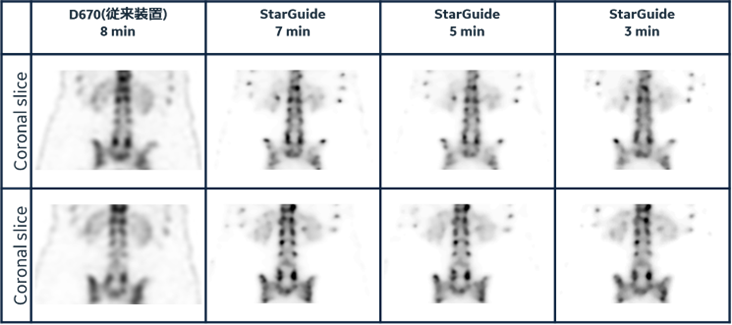

フォーカスモードを使用することで従来装置よりも短い時間で高画質化を実現